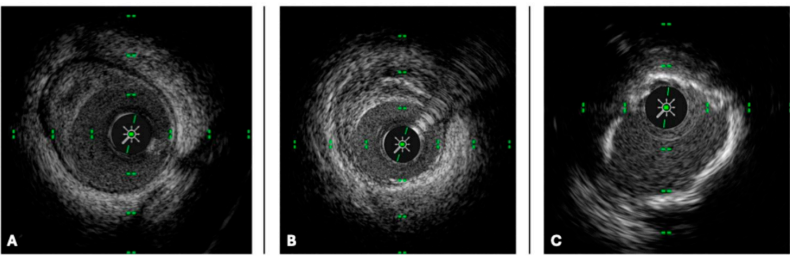

图2 冠状动脉的IVUS横断面图像

注:三种不同类型的动脉粥样硬化斑块:(A)脂质斑块,(B)纤维化斑块,(C)钙化斑块